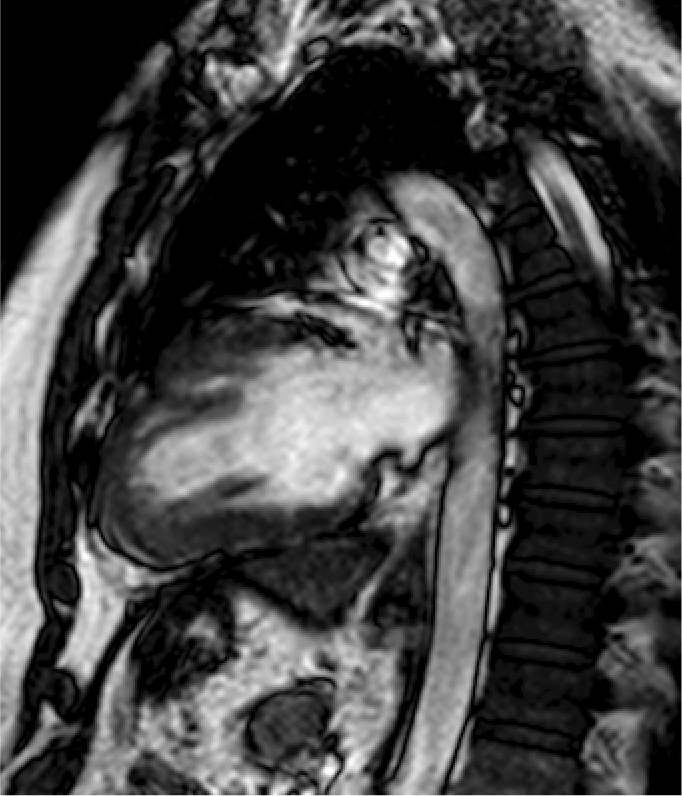

Resonancia magnética cardiaca

La resonancia magnética cardiaca es un una técnica de imagen que permite estudiar detalladamente y en una sola exploración la función y la estructura del corazón. Este auxiliar diagnóstico utiliza un potente campo magnético, sin radiación, para generar imágenes detalladas de las estructuras del corazón.

La resonancia magnética esta indicada en la evaluación de las cardiopatías congénitas tanto en el niño como en el adulto, en la evaluación de la perfusión miocárdica (resonancia cardiaca con gadolinio), de la función cardiaca, de las enfermedades del músculo cardiaco (miocardiopatías), tumores del corazón y del tejido que rodea al corazón (pericardio).